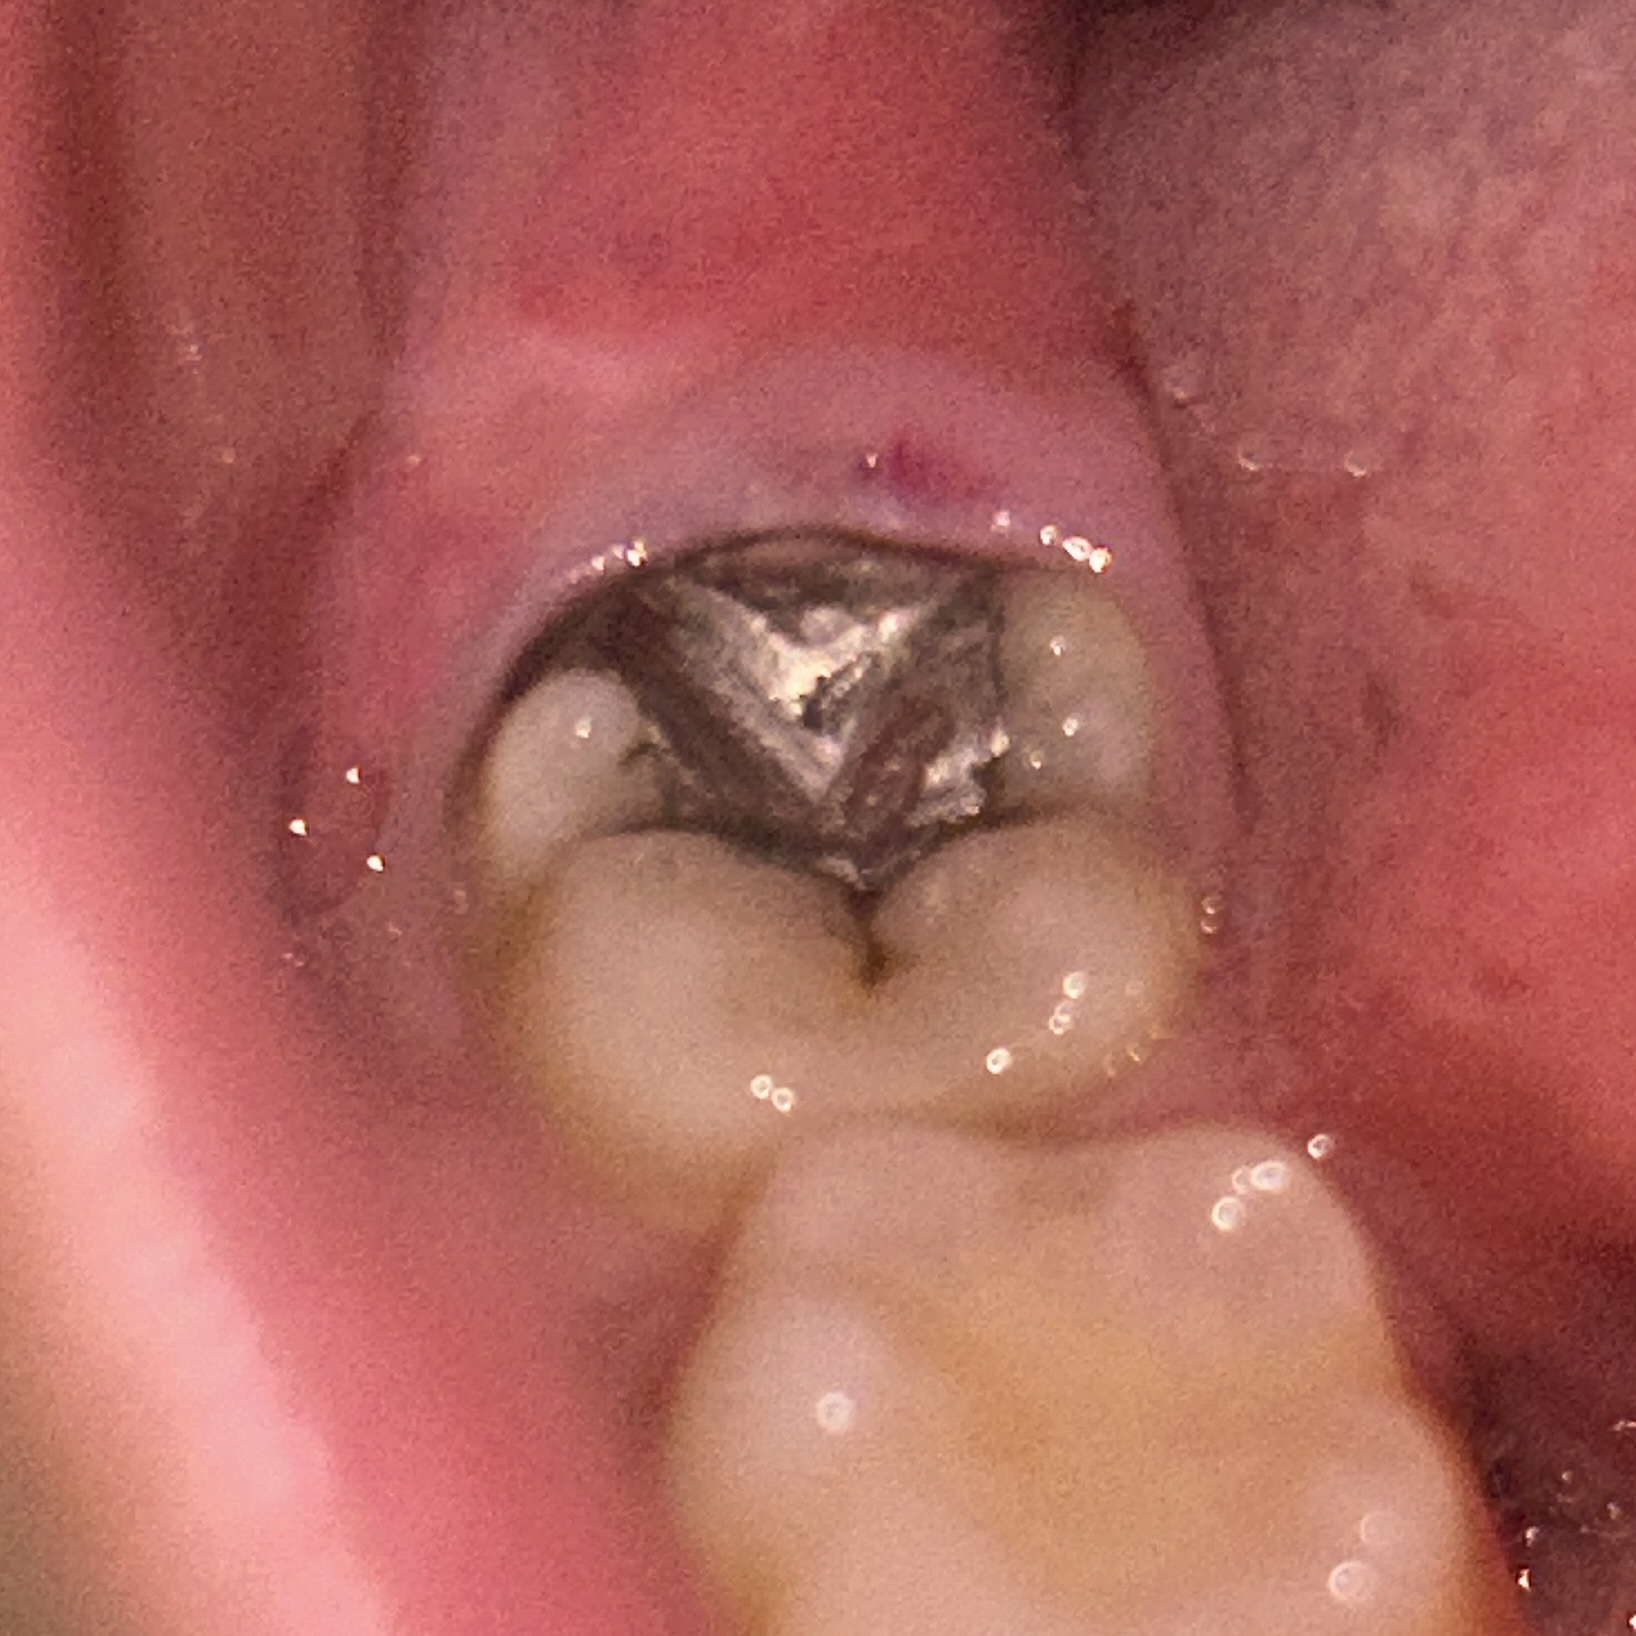

13 ตุลาคม 2568 08:44:26 #1 https://haamor.com/media/create_topic/20251013084137.jpeg รู้สึกเหมือนเหงือกบวม ถ้ามีอะไรโดน (กินข้าว/แปรงฟัน) จะรู้สึกเจ็บนิดๆ แต่ถ้าอยู่เฉยๆ ก็ไม่ปวดไม่เจ็บอะไร อันนี้หายเองได้ไหมคะ หรือต้องไปหาหมอ กินยาอะไร แล้วก็ตรงฟันที่อุดไว้มันผุเพิ่มหรือเปล่าคะ |

29 ตุลาคม 2568 11:55:06 #2 ภาพที่เห็น เป็นลักษณะของเหงือกบวม ฟันบนอาจมากัดกระทบด้วย คงไม่สามารถหายเอง ควรไปพบทันตแพทย์ เพื่อวินิจฉัย และรักษา ส่วนฟันที่อุดไว้เดิม จะผุต่อหรือไม่ ต้องตรวจ และเอกซเรย์เพิ่มเติม สรุป ควรพบทันตแพทย์ไม่สามารถหายเอง